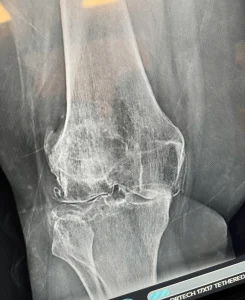

These are before/after X-rays of a patient’s right knee after getting stem cell therapy at Stem Cell Carolina. The “before” X-ray was taken in April 2021 before this patient had adipose-derived stem cells with PRP. The X-ray with red circles shows where there is an increase in joint space if you compare it to the “before” X-rays.